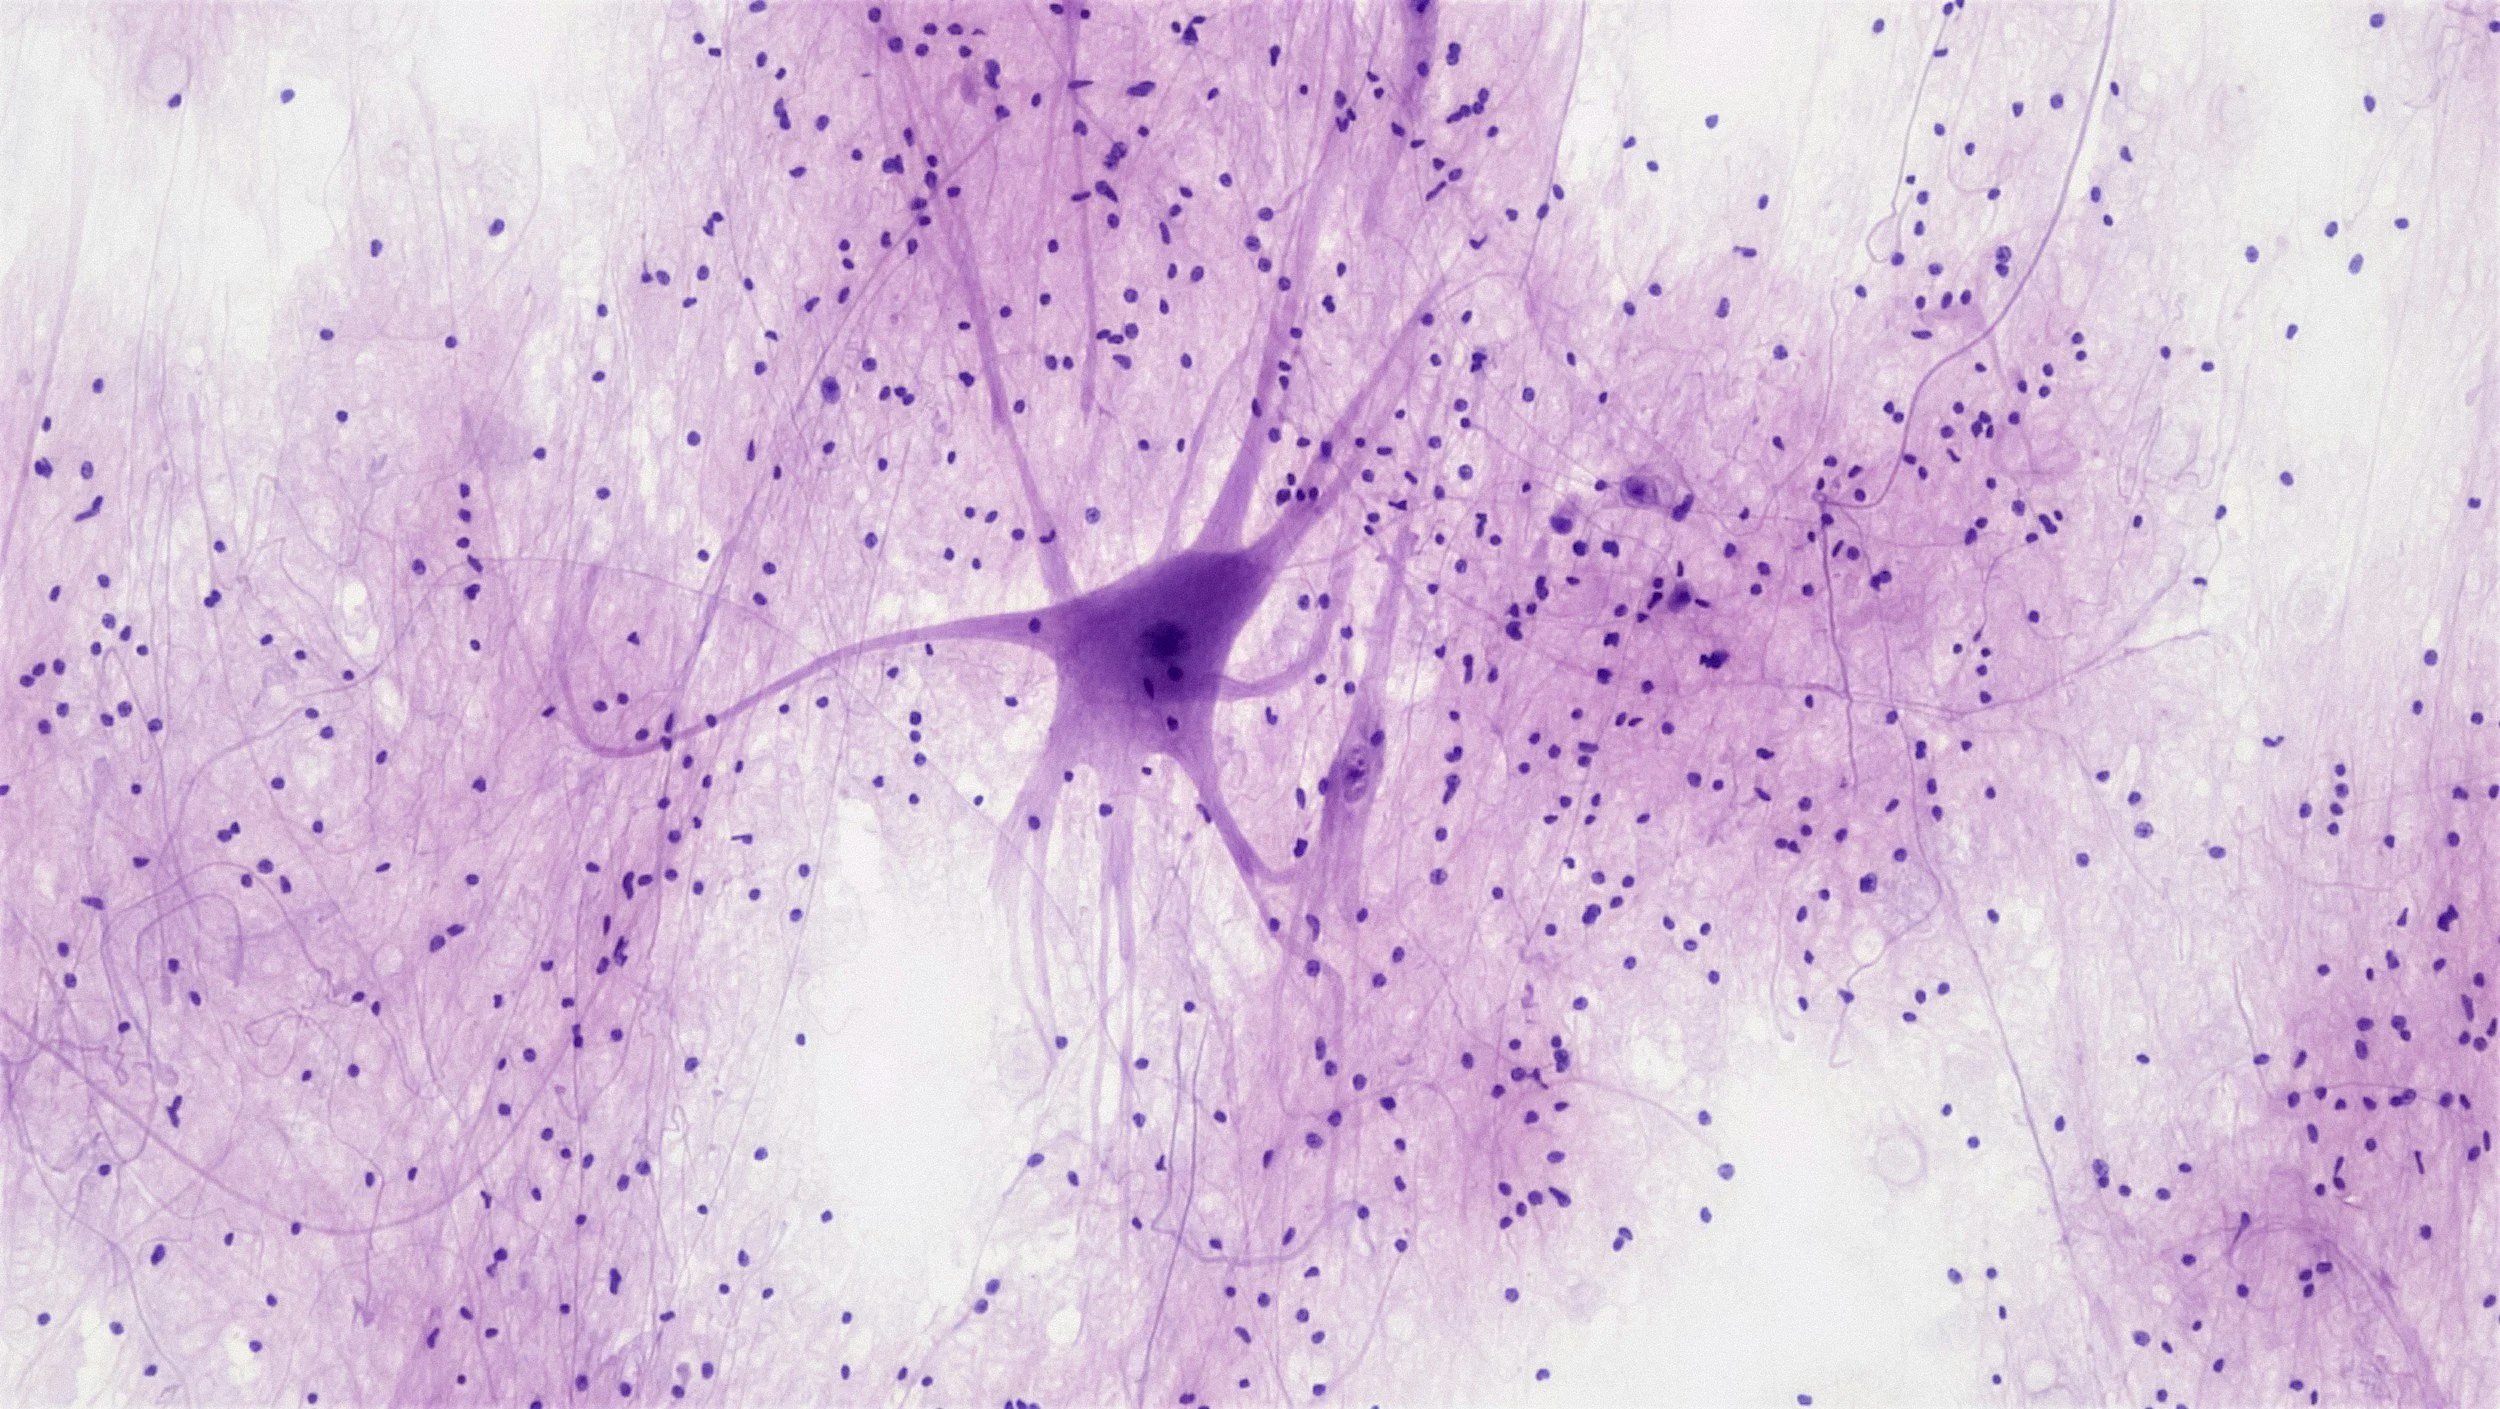

This article examines a review focused on Ashwagandha's role in treating brain disorders. The study discusses neuroactive phytoconstituents in Ashwagandha, their mechanisms of action, and the herb's effects on conditions like anxiety, Alzheimer's, and depression. While highlighting the lack of toxicity and the potential benefits as suggested by preclinical studies and patents, the review also notes the need for further research to understand the underlying mechanisms fully and to establish clinical efficacy.